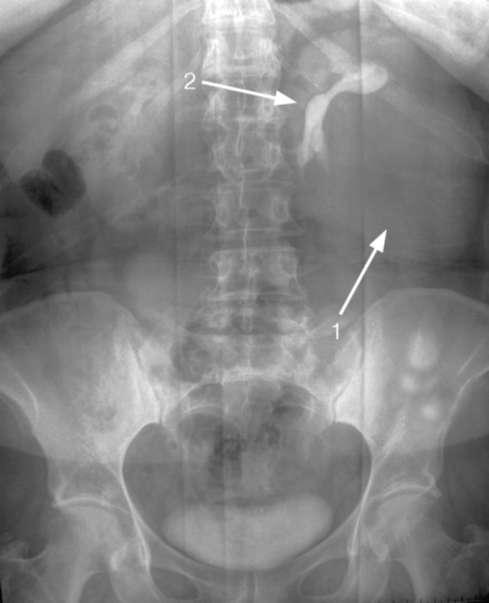

Медицинские изображения: Обзорная рентгенография урография

Раздел: Фокус на знании